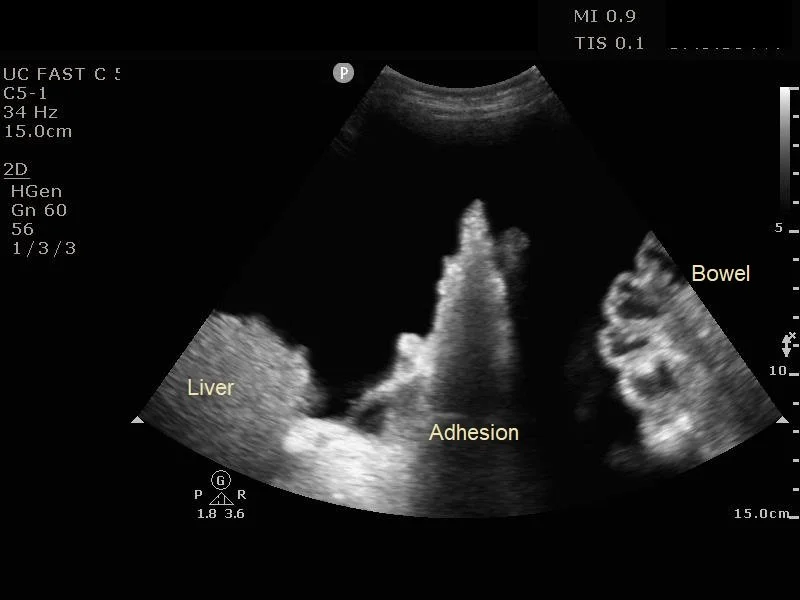

For initial evaluation for a fluid pocket, a low-frequency probe such as the curvilinear probe should be used (14). The ideal fluid pocket should be about 3-5 cm in depth between the abdominal wall and viscera / bowel loops. It is important to fan the probe through in multiple angles as bowel loops can appear in all directions. Also evaluate for any adhesions to the abdominal wall, commonly located in the areas of surgical scars. Observe the intended pocket in all phases of respiration as abdominal viscera and bowel loops can change position with respiratory variation. Before committing to a site, using a high frequency linear probe to ensure there are no blood vessels traversing the intended puncture site. This can minimize the risk of inadvertent blood vessel puncture and subsequent hemoperitoneum.